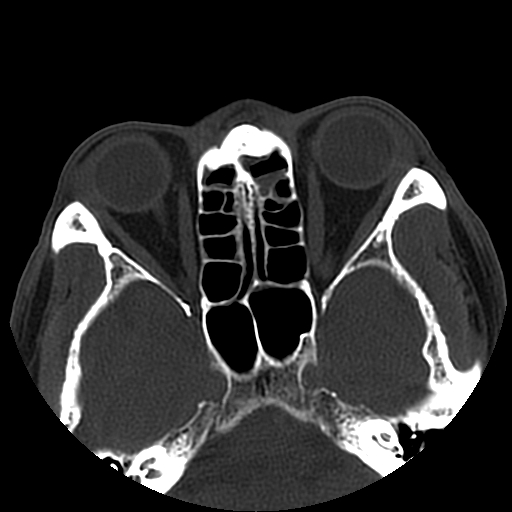

以下是引用liaoqiang在2008-7-16 21:15:00的发言:[br]右侧鼻骨骨折

以下是引用zxd95在2008-7-16 21:39:00的发言:[br]右侧上颌骨额突骨折。[br][br][br][br]